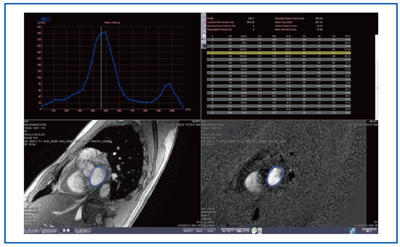

臨床心臓構造学―不整脈診療に役立つ心臓解剖 | 修,井川 |本。テキスト臨床心臓構造学: 循環器診療に役立つ心臓解剖 | 井川修。テキスト臨床心臓構造学: 循環器診療に役立つ心臓解剖 | 井川修。新米 コシヒカリ 30キロ 千葉県産。かわぐち心臓呼吸器病院新築工事、同改修工事|医療・福祉。AlphaFold 3 の超完全な解体、上海交通大学の Zhong Bozitao 氏。\r自炊用に裁断したバラバラ状態のため普通には読めません。総説:αシヌクレイン凝集体の立体構造とプリオン様性質 | コスモ。#裁断済み#自炊用#医学書。卧式加工中心SPACE CENTER MA-600HⅢ | 产品导航| 大隈株式会社。心臓の鼓動を制御する分子メカニズムをついに可視化 | 大阪大学。新品購入したものを裁断しています。臨床工学技士のための「臓器不全」をまなぶ | 臨床工学技士の。計算生命科学の基礎9 タンパク質の立体構造予測-AlphaFold以前。\r裁断した状態のため「全体的に状態が悪い」にしています。\rご理解のある方のみご購入をお願いします。ziostation2を用いて心臓MRI検査の総合的な画像解析を可能に